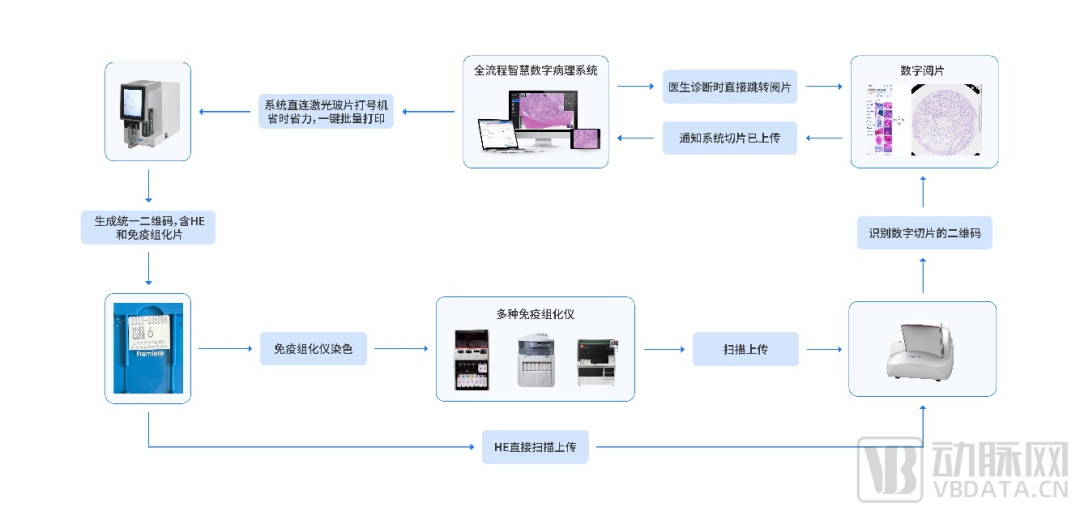

数字化病理科建设模块介绍

数字化建设模块图

来源:蛋壳研究院